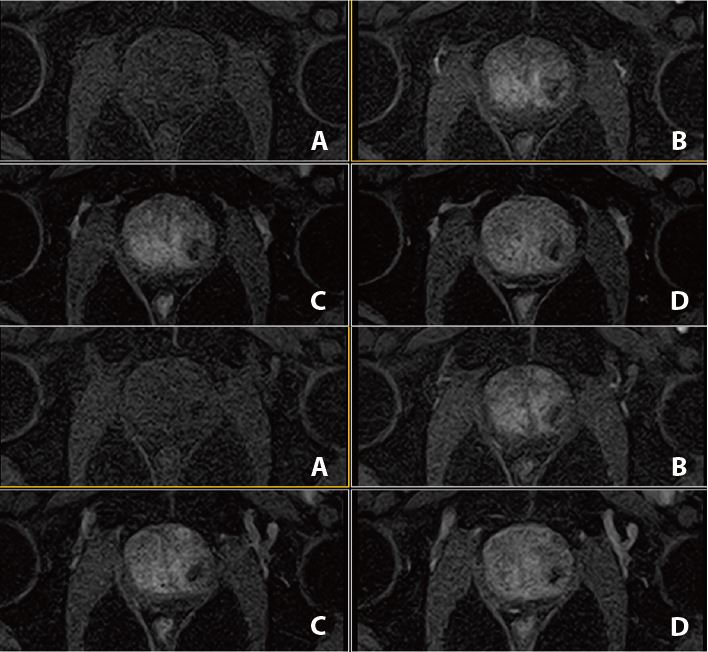

Рис. 3. Аксиальне DWI – A=b0, B=Iso b800, C=Iso b1000 e, D=Iso ADC (за протоколом mpMR)

Рис. 4. Динаміка. Аксіал (12 фаз) : A=1a phase pre, B=3a phase pos, C=6a phase pos, D=12a phase (згідно протоколу m pMR)